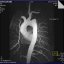

coronaro TC